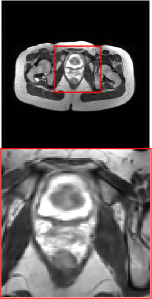

Figure 5 provides the qualitative comparison of the various methods on the four datasets at a scale of 4. The top, second, third, and bottom rows are the SR results under the FastMRI, clinical brain, clinical tumor and clinical pelvic datasets, respectively. The red boxes indicate the zoom-in region of complicated anatomical structures along with their corresponding error maps. Note that the brighter textures in the error maps, the lower the quality of the reconstructed images. As can be seen, compared to methods based on Transformers and CNNs, diffusion-based methods like DisC-Diff and DiffMSR (Ours) are capable of reconstructing high-realistic images with promising reconstruction metric scores (PSNR and SSIM). Nevertheless, while DisC-Diff can reconstruct high-precision MR images, it does not preserve the structure present in the original HR images, introducing some additional information that can affect medical diagnosis. In contrast, our method combines DM and PLWformer, which can preserve the original image’s structure while restoring high-frequency information.

In this section, we present more visual qualitative comparisons. Figures 8, 9, 10, and 11 show the reconstruction results of each method in FastMRI, clinical brain, clinical tumor, and clinical pelvic, respectively. As can be seen, although DisC-Diff can reconstruct MR images with high-frequency information, it fails to preserve the structure and content of the original Target HR image effectively, resulting in image distortion. In contrast, our proposed DiffMSR can restore high-frequency information while preserving the structure of the original HR image, indicating the effectiveness of the joint use of DM and PLWformer.